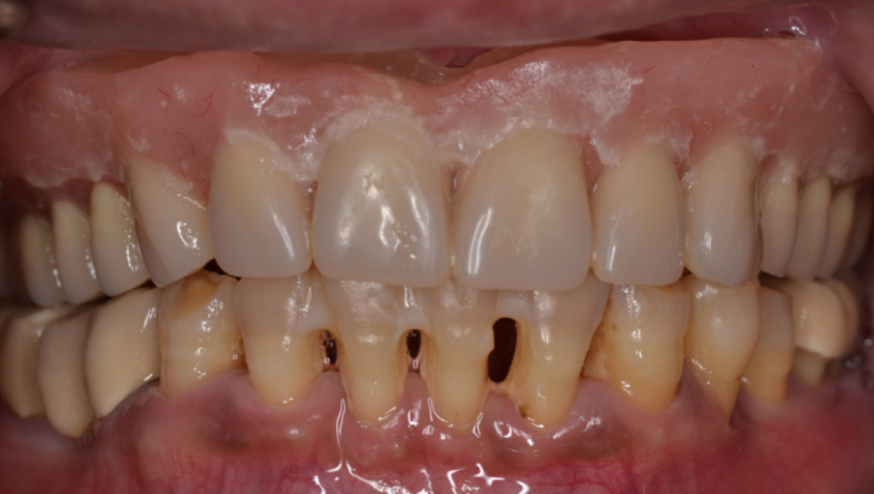

44-річному пацієнту раніше видалено всі верхні зуби та встановлено негайний суцільний знімний протез з правильним співвідношенням між прикусом та накладним протезом.

Ротова порожнина пацієнта, із встановленим протезом на місце, була просканована тим самим апаратом для комп'ютерної томографії. Скан протезу був співставлений із записом комп'ютерної томографії верхньої щелепи задля планування оптимального протезування на імплантах. (зображення 1 та 2)